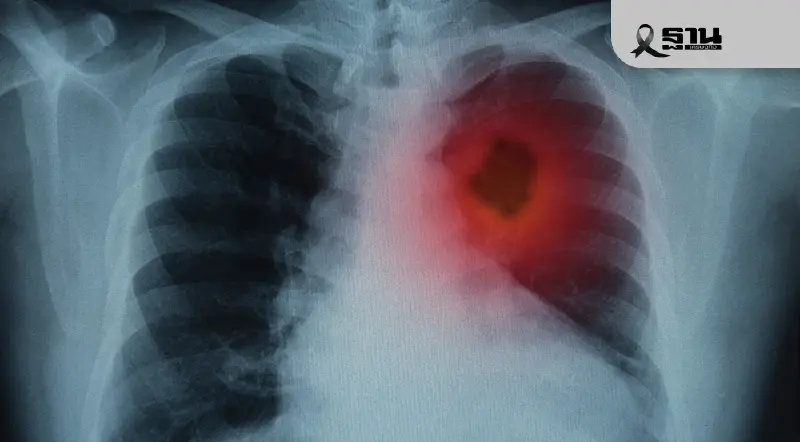

ตระหนักรู้เรื่อง “ปอด” การผ่าตัดทรวงอกรักษาโรคสำหรับผู้ป่วย

แพทย์แนะรักษา “โรคปอด“ ด้วยการผ่าตัดส่องกล้องสำเร็จถึง 80-90% รักษาผู้ป่วยซับซ้อนและผู้สูงอายุได้ ลดภาวะแทรกซ้อนจากการผ่าตัดต่ำกว่า 1%

รศ.นพ.ศิระ เลาหทัย ศัลยแพทย์ผู้เชี่ยวชาญด้านการผ่าตัดปอดและทรวงอก ประจำโรงพยาบาลวชิรพยาบาล กล่าวว่า การรักษาโรคปอดและการผ่าตัดทรวงอกในประเทศไทย ได้พัฒนาอย่างก้าวกระโดดในช่วงไม่กี่ปีที่ผ่านมา โดยมีเป้าหมายเพื่อนำมาตรฐานการรักษาเข้าสู่ระดับนานาชาติ